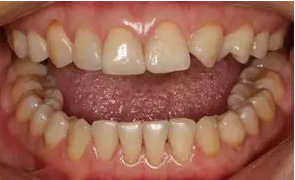

術(shù)前微笑照

術(shù)前全牙弓咬合照

術(shù)前全牙弓非咬合照